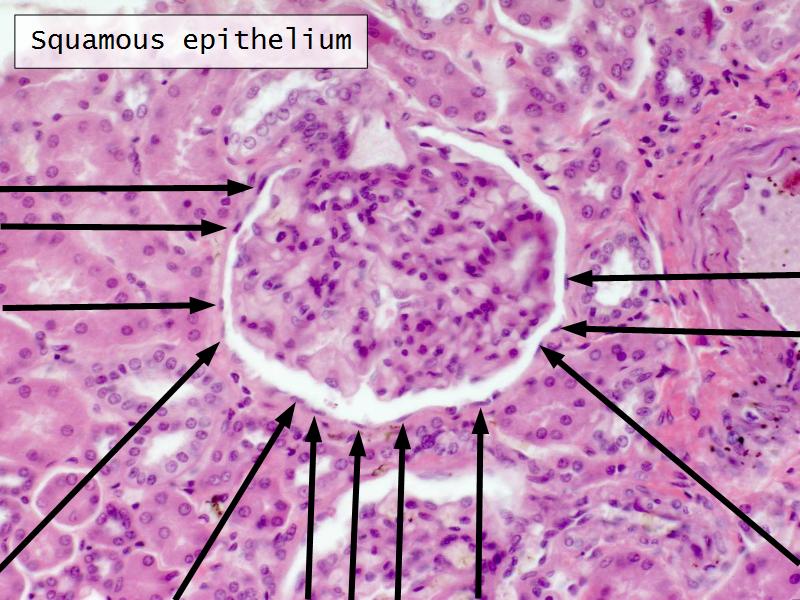

- The renal corpuscle

Q13: Name 1 epithelium for each.

Q13: Name 1 epithelium for each.

- Kidney = cuboidal, squamous

- Liver = squamous, cuboidal